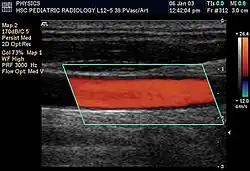

Spectral duplex scan of the common carotid artery

Duplex ultrasonography sometimes refers to Doppler ultrasonography or spectral Doppler ultrasonography.[3] Doppler ultrasonography consists of two components: brightness mode (B-mode) showing anatomy of the organs, and Doppler mode (showing blood flow) superimposed on the B-mode. Meanwhile, spectral Doppler ultrasonography consists of three components: B-mode, Doppler mode, and spectral waveform displayed at the lower half of the image. Therefore, "duplex ultrasonography" is a misnomer for spectral Doppler ultrasonography, and more exact name should be "triplex ultrasonography".[3]

Duplex scan of the common carotid artery

Colour Doppler shows the direction of the blood flow in red or blue (either towards or away from the transducer). Meanwhile, spectral Doppler not only shows the direction of blood flow, it also shows the phases (pulsatility) and acceleration of the blood flow. Any sudden changes in direction of blood flow produces audible sounds on the ultrasound machine.[3]

In spectral Doppler, the y-axis shows the direction and velocity of the flow. Meanwhile, the x-axis (as known as "baseline") shows the flow over time. The gradient at any point on the waveform would therefore shows the acceleration of the flow. In "antegrade" flow, the blood flows according to the normal flow within the circulatory system (e.g. veins flow towards the heart while arteries flows away from the heart). In "retrograde" flow, the flow would reverse (e.g. veins flow away from heart or arteries flow towards the heart). However, "retrograde" flow can be both abnormal or normal. For example, in portal hypertension, there is an abnormal portal venous flow where it flows away from the liver (hepatofugal flow) instead of the normal flow towards liver (hepatopetal flow). In jugular venous pressure waveform of the internal jugular vein, the retrograde "a" waveform is a normal flow due to right atrium contraction. Both antegrade or retrograde flow can be either towards or away from the probe transducer, depending on the position of the probe relative to the blood flow. Blood flow toward the transducer would appear above the baseline while blood flows away from the transducer will appear below the baseline. Waveform of the flow can be classified as: pulsatile (as in arteries), phasic (as in veins), non-phasic (as in diseased veins), and aphasic (no flow). Spectral broadening (thickness of the waveform) increases from large vessels (plug flow) to medium vessels (laminar flow) to small/stenotic/diseased vessels (turbulent flow) due to a larger variety of blood with different ranges of velocities in those with turbulent flow.[3]